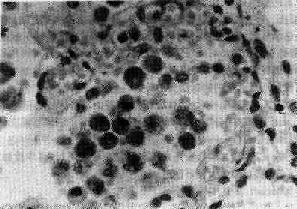

较长期的静脉性充血,使局部组织内代谢中间产物蓄积,从而损害毛细血管,使其通透性增高,加之淤血时小静脉和毛细血管内流体静力压升高,导致局部组织发生水肿,严重时甚至发生漏出性出血。如肺淤血时,肺泡壁毛细血管扩张、充血,严重时肺泡腔内可出现水肿液,甚至出血。若肺泡腔内的红细胞被巨噬细胞吞噬,其血红蛋白变为含铁血黄素,使痰呈褐色。这种巨噬细胞常在左心衰竭的情况下出现,因而被称为心力衰竭细胞(heart failure cell)(图3-1)。

图3-1 慢性肺淤血

肺泡壁毛细血管充血,肺泡腔内漏出性出血并出现心力衰竭细胞